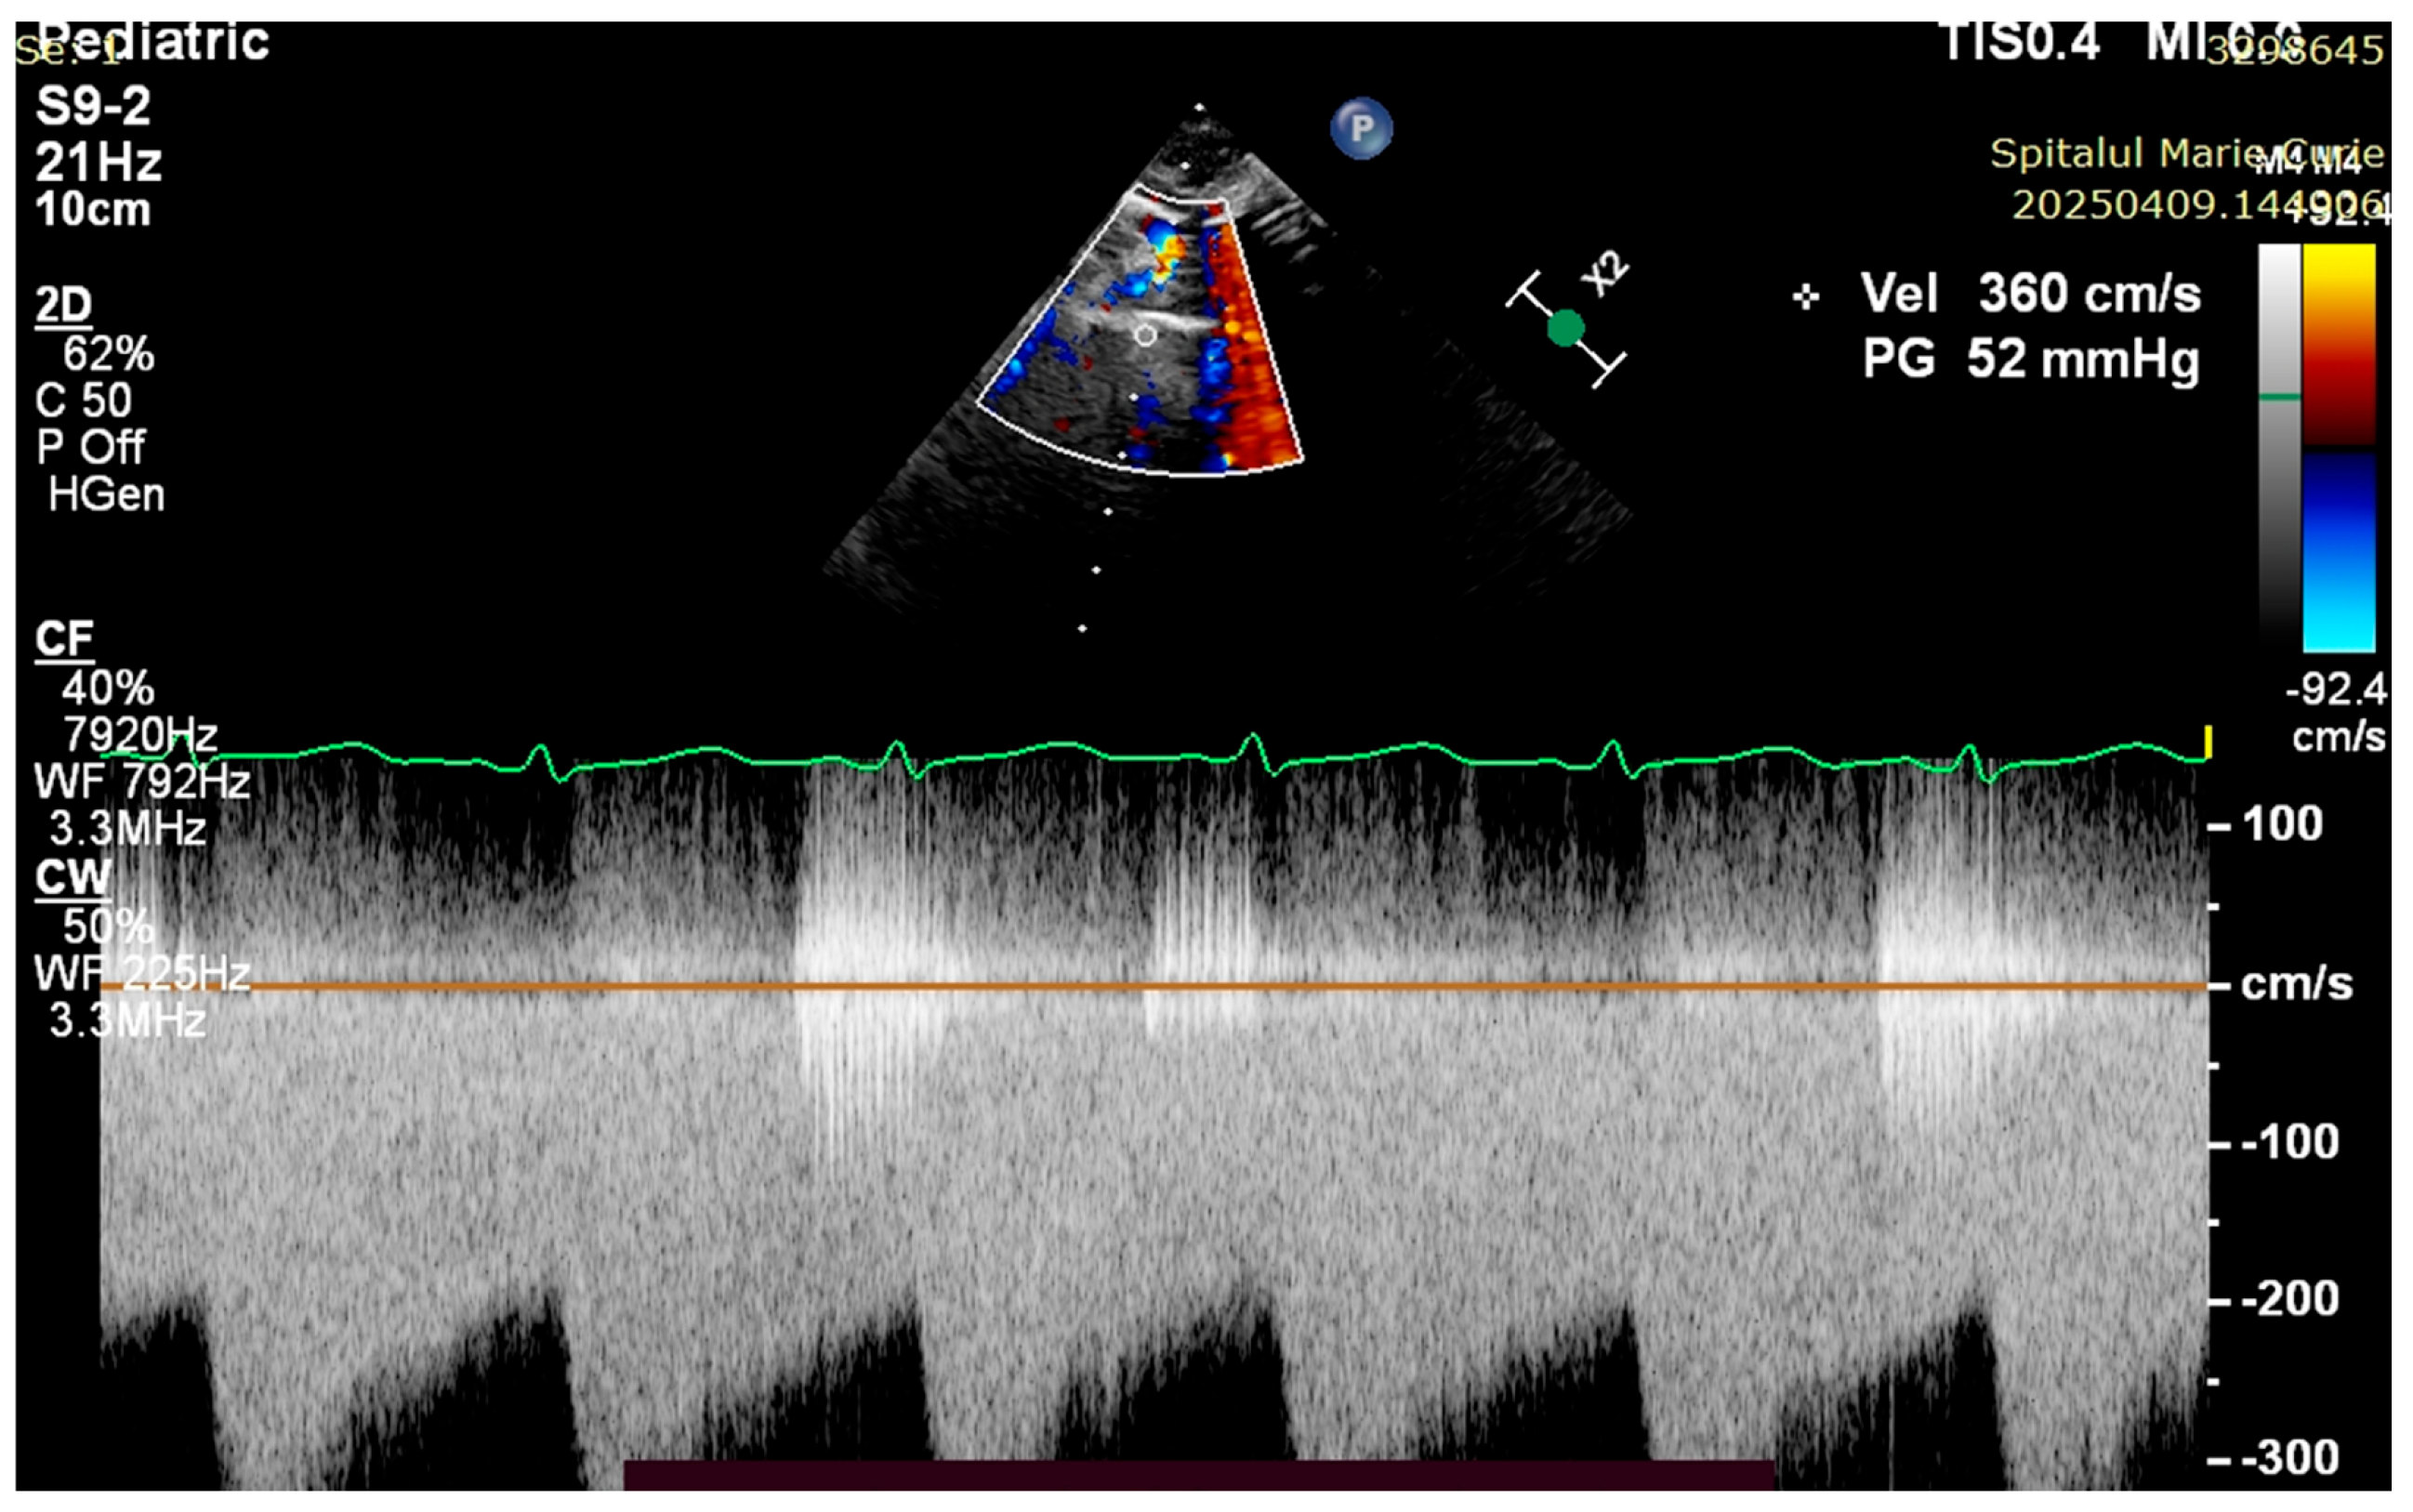

4. Case Reports